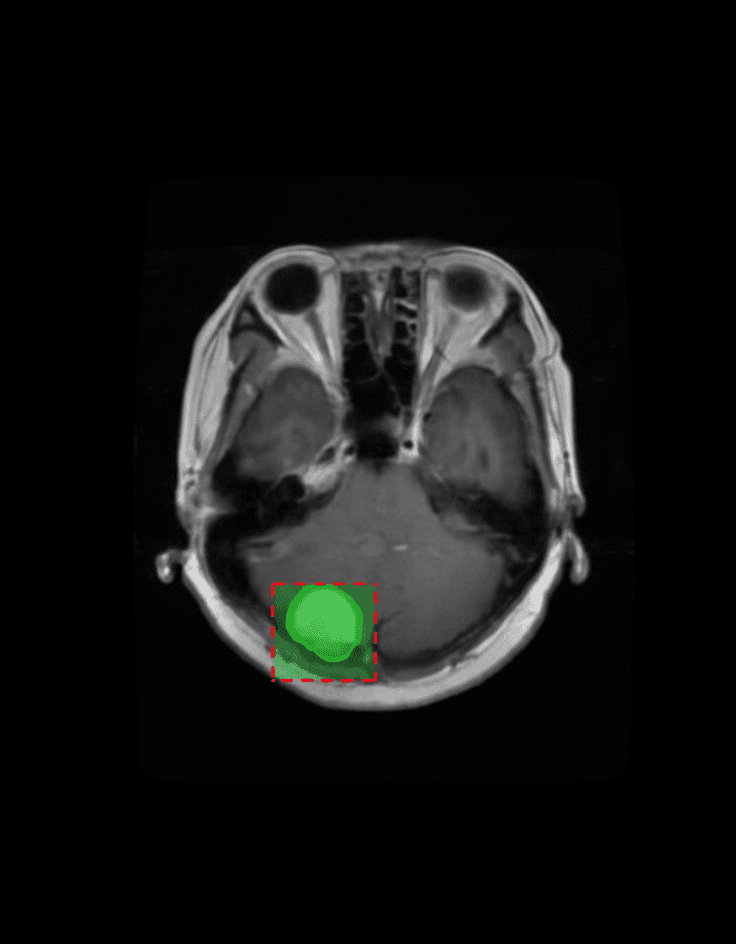

Our AI platform analyzes MRI scans using multi-sequence 3D deep learning models, automatically identifying and measuring tumor regions.

3D MRI Segmentation

Multi-sequence deep learning models for precise volumetric tumor segmentation